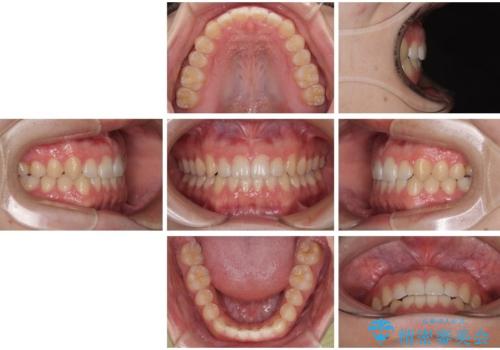

治療症例の内容

- 20代男性

- インビザラインモデレート

- 治療期間

- 11ヶ月

- 治療回数

- 5-10回

- 60万円(税込)費用は治療当時の料金となります